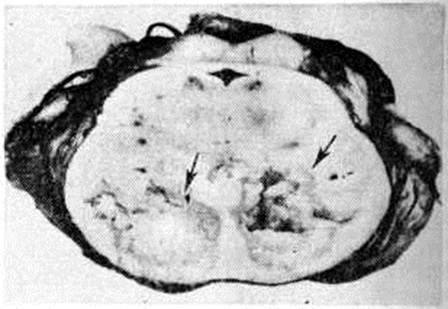

Геморрагический инсульт, как правило, возникает при заболеваниях, протекающих с повышенным артериальное давление. Это обусловлено тем, что сосудистые кризы (смотри полный свод знаний), характерные для гипертонической болезни (смотри полный свод знаний) и артериальной гипертензии (смотри полный свод знаний Гипертензия артериальная), приводят к морфологический изменениям стенок внутримозговых сосудов с нарушением их проницаемости — плазматическому пропитыванию (рисунок 1), некрозам (рисунок 2), образованию микроаневризм (рисунок 3) и их разрывам. Разрыв врождённых артериальных и артериовенозных аневризм может протекать на фоне нормального давления. Преимущественная локализация и характер геморрагий определяются особенностями ангиоархитектоники различных отделов мозга. При гипертонической болезни наиболее тяжёлым изменениям подвергаются сосуды подкорковых узлов и зрительного бугра. Это объясняется отхождением глубоких ветвей под прямым углом от средней мозговой артерии, являющейся продолжением внутренней сонной артерии, и незначительным числом анастомозов сосудов в этой области. В связи с этим на вскрытии кровоизлияния наиболее часто (40%) обнаруживаются в подкорковых узлах с распространением в прилежащее белое вещество (так называемый латеральные кровоизлияния, то есть расположенные латерально от внутренней капсулы, рисунок 4). Второе место по частоте (16%) занимают обширные кровоизлияния, разрушающие подкорковые узлы, внутреннюю капсулу, зрительный бугор (так называемый смешанные кровоизлияния — рисунок 5). Кровоизлияния в зрительный бугор (так называемый медиальные — рисунок 6) составляют 10%, в мозжечок — 6—10%, в мост мозга — 5% от общего числа внутримозговых геморрагий. Кровоизлияния только в белое вещество полушарий мозга встречаются крайне редко. Подразделение полушарных кровоизлияний на латеральные, медиальные и смешанные имеет особое значение в связи с хирургическим лечением геморрагического Инсульт.

Кровоизлияния типа гематомы сопровождаются образованием полости, содержащей жидкую кровь или свёртки крови; они составляют 85% внутримозговых кровоизлияний, наиболее часто развиваются в подкорковых узлах, реже в мозжечке. Основной механизм развития гематомы — разрыв патологически изменённого сосуда (рисунок 7). Формирование гематомы идёт путём раздвигания кровью вещества мозга с перемещением его участков, что возможно благодаря резервным пространствам (желудочки, подпаутинное пространство). Размеры гематомы при этом превышают объем разрушенного кровью вещества, сдавление окружающих отделов незначительно; лишь при кровоизлиянии в мозжечок сдавление вещества мозга весьма существенно в связи с анатомическими особенностями задней черепной ямки (рисунок 8).